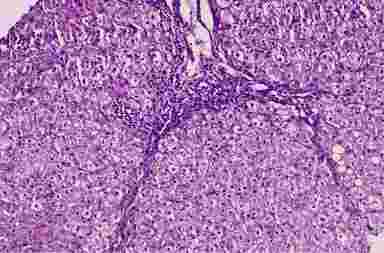

Хронический вирусный гепатит B

Рис. 4.4. Хронический вирусный гепатит B (биоптат печени, окраска г/э, х100). Фиброзные септы с нарушением долькового строения печени, формирующаяся ложная долька. Гидропическая дистрофия гепатоцитов

Морфологические признаки хронического гепатита В. В биоптатах печени обнаруживают дистрофию и некроз гепатоцитов, воспалительную клеточную инфильтрацию и фиброзные изменения в дольках и портальных трактах (табл.4.3). Очень характерна гидропическая дистрофия гепатоцитов (рис. 4.4), реже - крайняя ее форма – баллонная дистрофия. Некроз гепатоцитов имеет вид цитолитического (колликвационного) или “Ацидофильного” (коагуляционного). В последние годы приводятся данные об апоптозе (программированной смерти) гепатоцитов. Повреждение и деструкция гепатоцитов обусловлены действием иммунных механизмов при участии Т-лимфоцитов, продукты распада клеток, в свою очередь, захватываются макрофагами. Поэтому очаги некроза паренхимы, как правило, содержат лимфоидно-макрофагальный инфильтрат (некро-воспалительная активность). Клетки инфильтрата (лимфоциты, макрофаги; в небольшом количестве плазмоциты и нейтрофилы) постоянно локализуются в портальных трактах.

При хроническом гепатите в ткани печени постоянно развиваются фиброзные изменения. В дольках на месте прежних мелких очагов некроза находят участки фиброза ретикулярной стромы. Воспалительная инфильтрация портальных трактов сопровождается их утолщением и фиброзом, после ступенчатых некрозов возникает перипортальный фиброз. На месте мостовидных некрозов образуются прослойки волокнистой соединительной ткани (порто-портальные и порто-центральные фиброзные септы). Фиброзные септы могут окружать формирующиеся регенераторные узлы, ложные дольки, что приводит к нарушению долькового строения печени (рис. 4.4) и в дальнейшем может вести к циррозу.